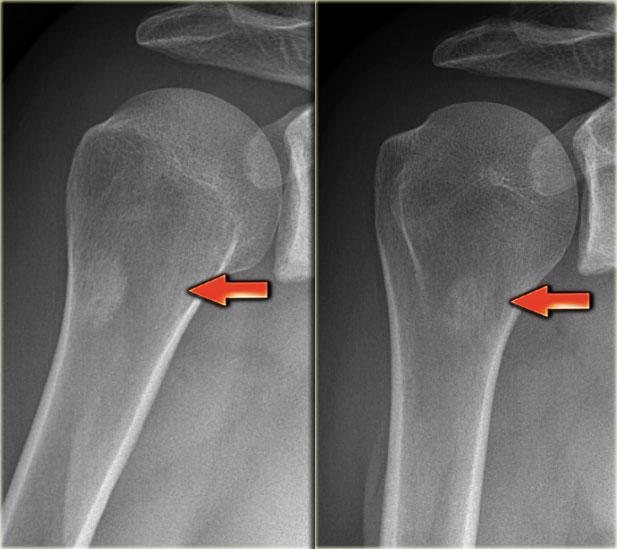

Đây là hình ảnh của một bệnh nhân có khối xơ cứng cạnh vỏ xương ở đầu trên xương cánh tay (trái).

Trường hợp này được xác định là vôi hóa phản ứng thứ phát sau chấn thương.

Lưu ý sự tương đồng với khối u cạnh vỏ xương ở một bệnh nhân khác (bên phải), được chẩn đoán xác định bằng sinh thiết là u xương cạnh màng xương (parosteal osteosarcoma).

Điều này cho thấy rằng việc phân biệt khối u với một quá trình phản ứng đôi khi có thể rất khó khăn trong một số trường hợp.

Khi một quá trình phản ứng có khả năng xảy ra hơn dựa trên tiền sử và đặc điểm hình ảnh, đôi khi vẫn cần theo dõi thêm.